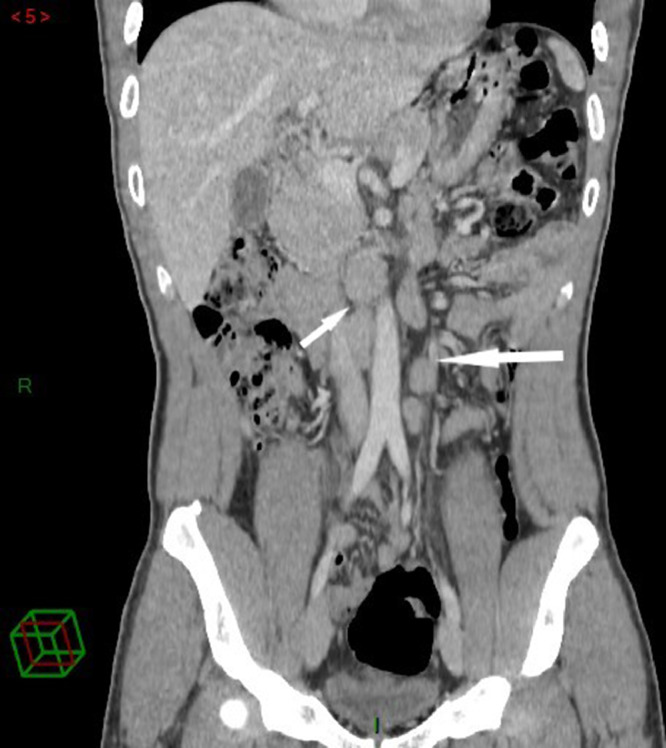

As part of an assessment of the extension of the disease, the patient had undergone a thoracoabdominipelvic scan and a positron emission tomography (PET) scan which did not show any notable abnormality apart from multiple lumboaortic lymphadenopathy (Fig. 3).

Thoracoabdominopelvic CT scan showing multiple coeliomesenteric abdominal lymphadenopathy (arrow).

On the other hand, multiple abdominal adenomegalies were discovered as part of the extension workup. This lymph node site could constitute the latent focus of tuberculosis in our patient.